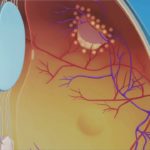

Retina is the innermost layer of eye ball. The image is formed by the optical apparatus of eye over the retina . It is very delicate part. Common diseases and there treatment facilities available at our centre are as follows:-

The retina is the membrane that covers the back of the eye. It is highly sensitive to light.

It converts any light that hits the eye into signals that can be interpreted by the brain. This process produces visual images, and it is how sight functions in the human eye.

Retinal blood vessel occlusion affects the eye, specifically the retina. The retina is the light-sensitive layer of tissue that lines the back of your eye. It’s covered with special cells called rods and cones that convert light into neural signals and send these signals on to the brain so you can see. The retina is vital for vision.